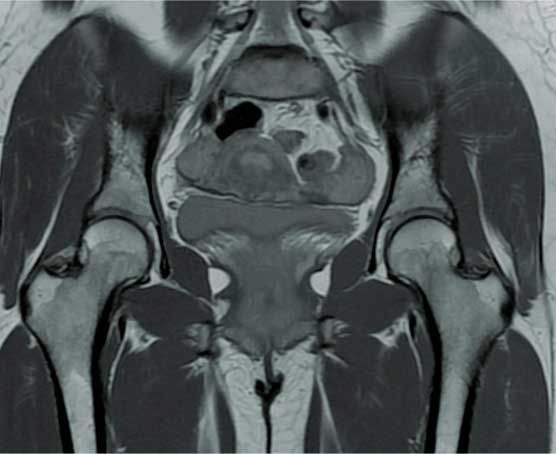

Fractura

de cadera

Es la pérdida de la continuidad del tejido óseo en la articulación de la cadera, producidas por caídas o traumatismos de alta energía, la cual se caracteriza por dolor intenso, incapacidad funcional, chasquidos, acortamiento y rotación de la pierna, el diagnóstico definitivo es por radiografía o tomografía.

¿Por qué se realiza?

El tratamiento en pacientes adultos regularmente es quirúrgico, el cual se realiza con implantes de metal que recuperan la anatomía normal de la articulación similar a la previa fractura, los cuales pueden ser clavos, placas, tornillos o prótesis.

Cuidados después de la intervención

La intención de un tratamiento de fractura siempre es movilizar al paciente lo más pronto posible, los tiempos para movilizar al paciente puede ser desde el primer día del tratamiento hasta algunas semanas dependiendo del tipo de fractura, tipo de paciente y el implante utilizado.

Resultados esperados

El objetivo es recuperar la función previo a la fractura con la misma fuerza, movimiento y estabilidad, esto se puede lograr si se realiza un diagnóstico adecuado y un tratamiento con una buena planeación.